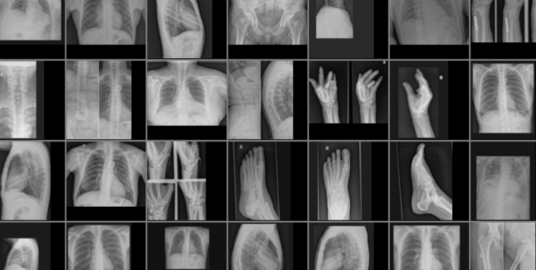

身体部位X射线图像数据集

数据集下载地址:http://m6z.cn/5yth1K

本数据集收集了来自身体各部位的X光图片